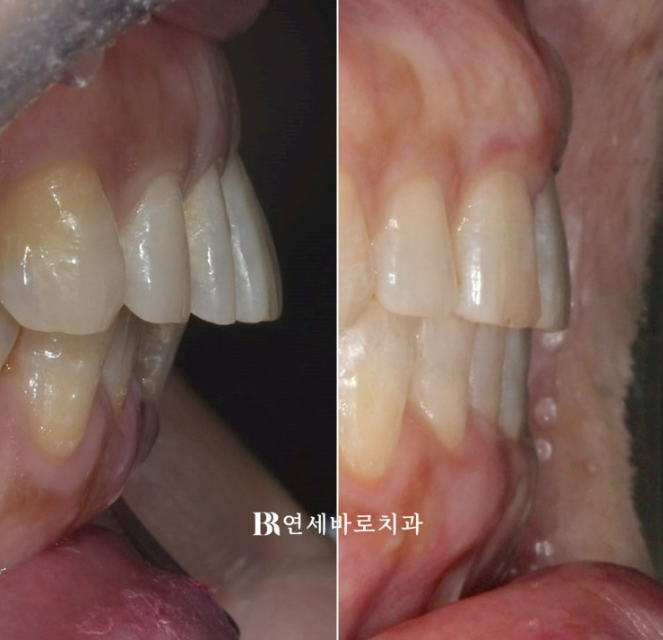

점점 돌출이 되었던 앞니가 다시 뒤로 들어가면서 제자리를 찾았습니다.

50대 치아벌어짐 적절한 치료계획과 적당한 갯수의 올바른 어태치먼트의 배치

각 치아마다 다른 전략을 세워 치료를 하면 가장 빠르고 좋은 결과를 만듭니다.